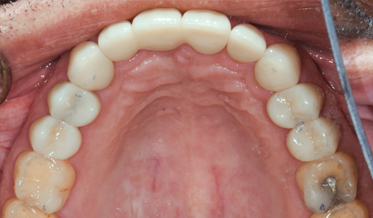

Use of Tuberosity Tissue Block for Tunneling Reconstruction of Class III Sockets With Simultaneous Implant Placement: A Case Report